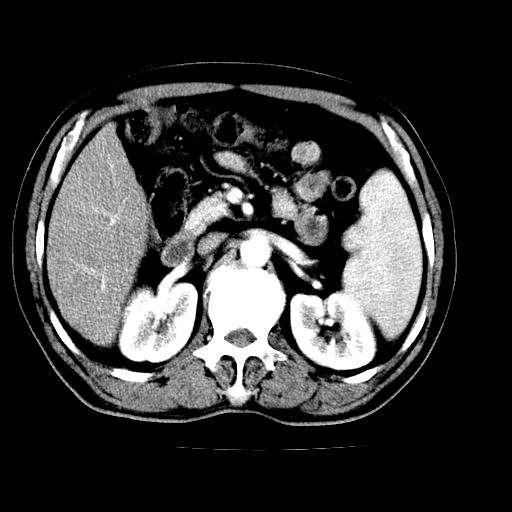

男,66岁,上腹部不适、黄染一周。彩超示:肝左叶占位,肝内胆管扩张,胆总管扩张,胆总管占位?

肝左叶不规则软组织肿块影,边缘不规整邻近肝实质受累分界不清;肝内胆管(左叶)明显扩张成“软藤状”,诊断:肝左叶胆管细胞癌。

左叶胆管细胞癌累及胆总管,门脉左支受侵,慢性胆囊炎胆结石,左肾小囊肿

支持肝左叶肝内胆管细胞癌伴胆总管及门脉左支受侵。